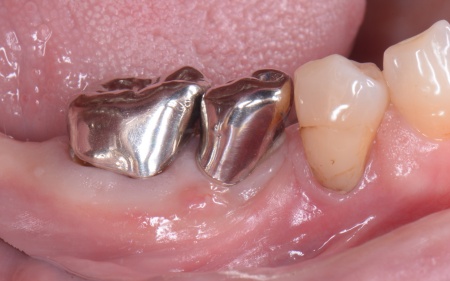

| カウンセリング | 拝見したところ、右下奥歯2本が噛むと痛む状態でした。 これらの歯は、以前神経を除去する処置を行っており、その後銀歯にされていたとのことです。 詳しく調べるためにレントゲン撮影を行った結果、どちらの歯も歯根が割れていることが確認できました。 歯根が割れた歯は元の状態に戻すことができず、そのまま放置すると炎症が広がって周囲の骨や隣接する歯に悪影響を及ぼすリスクがあります。 以上のことから、抜歯をしたうえで歯を補う治療が必要だと診断しました。 |